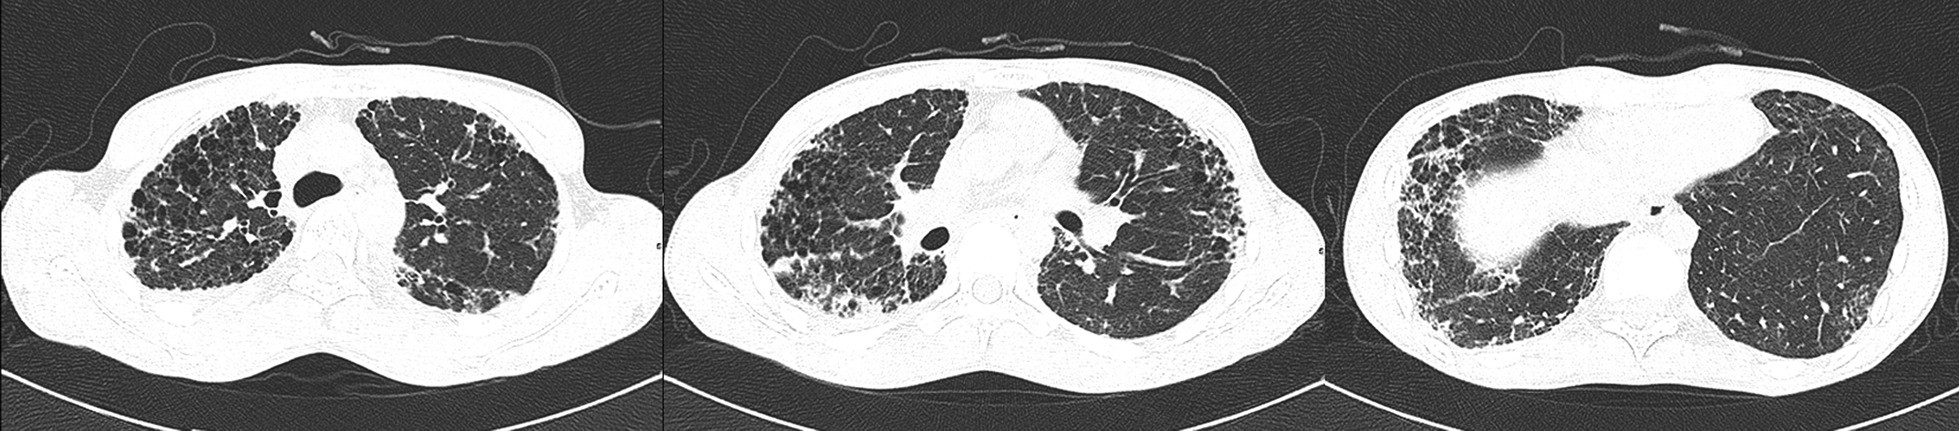

Fig. 2

High resolution computed tomography manifestation of the patient. Chest high resolution computed tomography scan showed mid- and upper-zone predominant bilateral peripheral reticulolinear shadows, interlobular septal thickening with associated traction bronchiectasis and honeycombing, compatible with pulmonary fibrosis